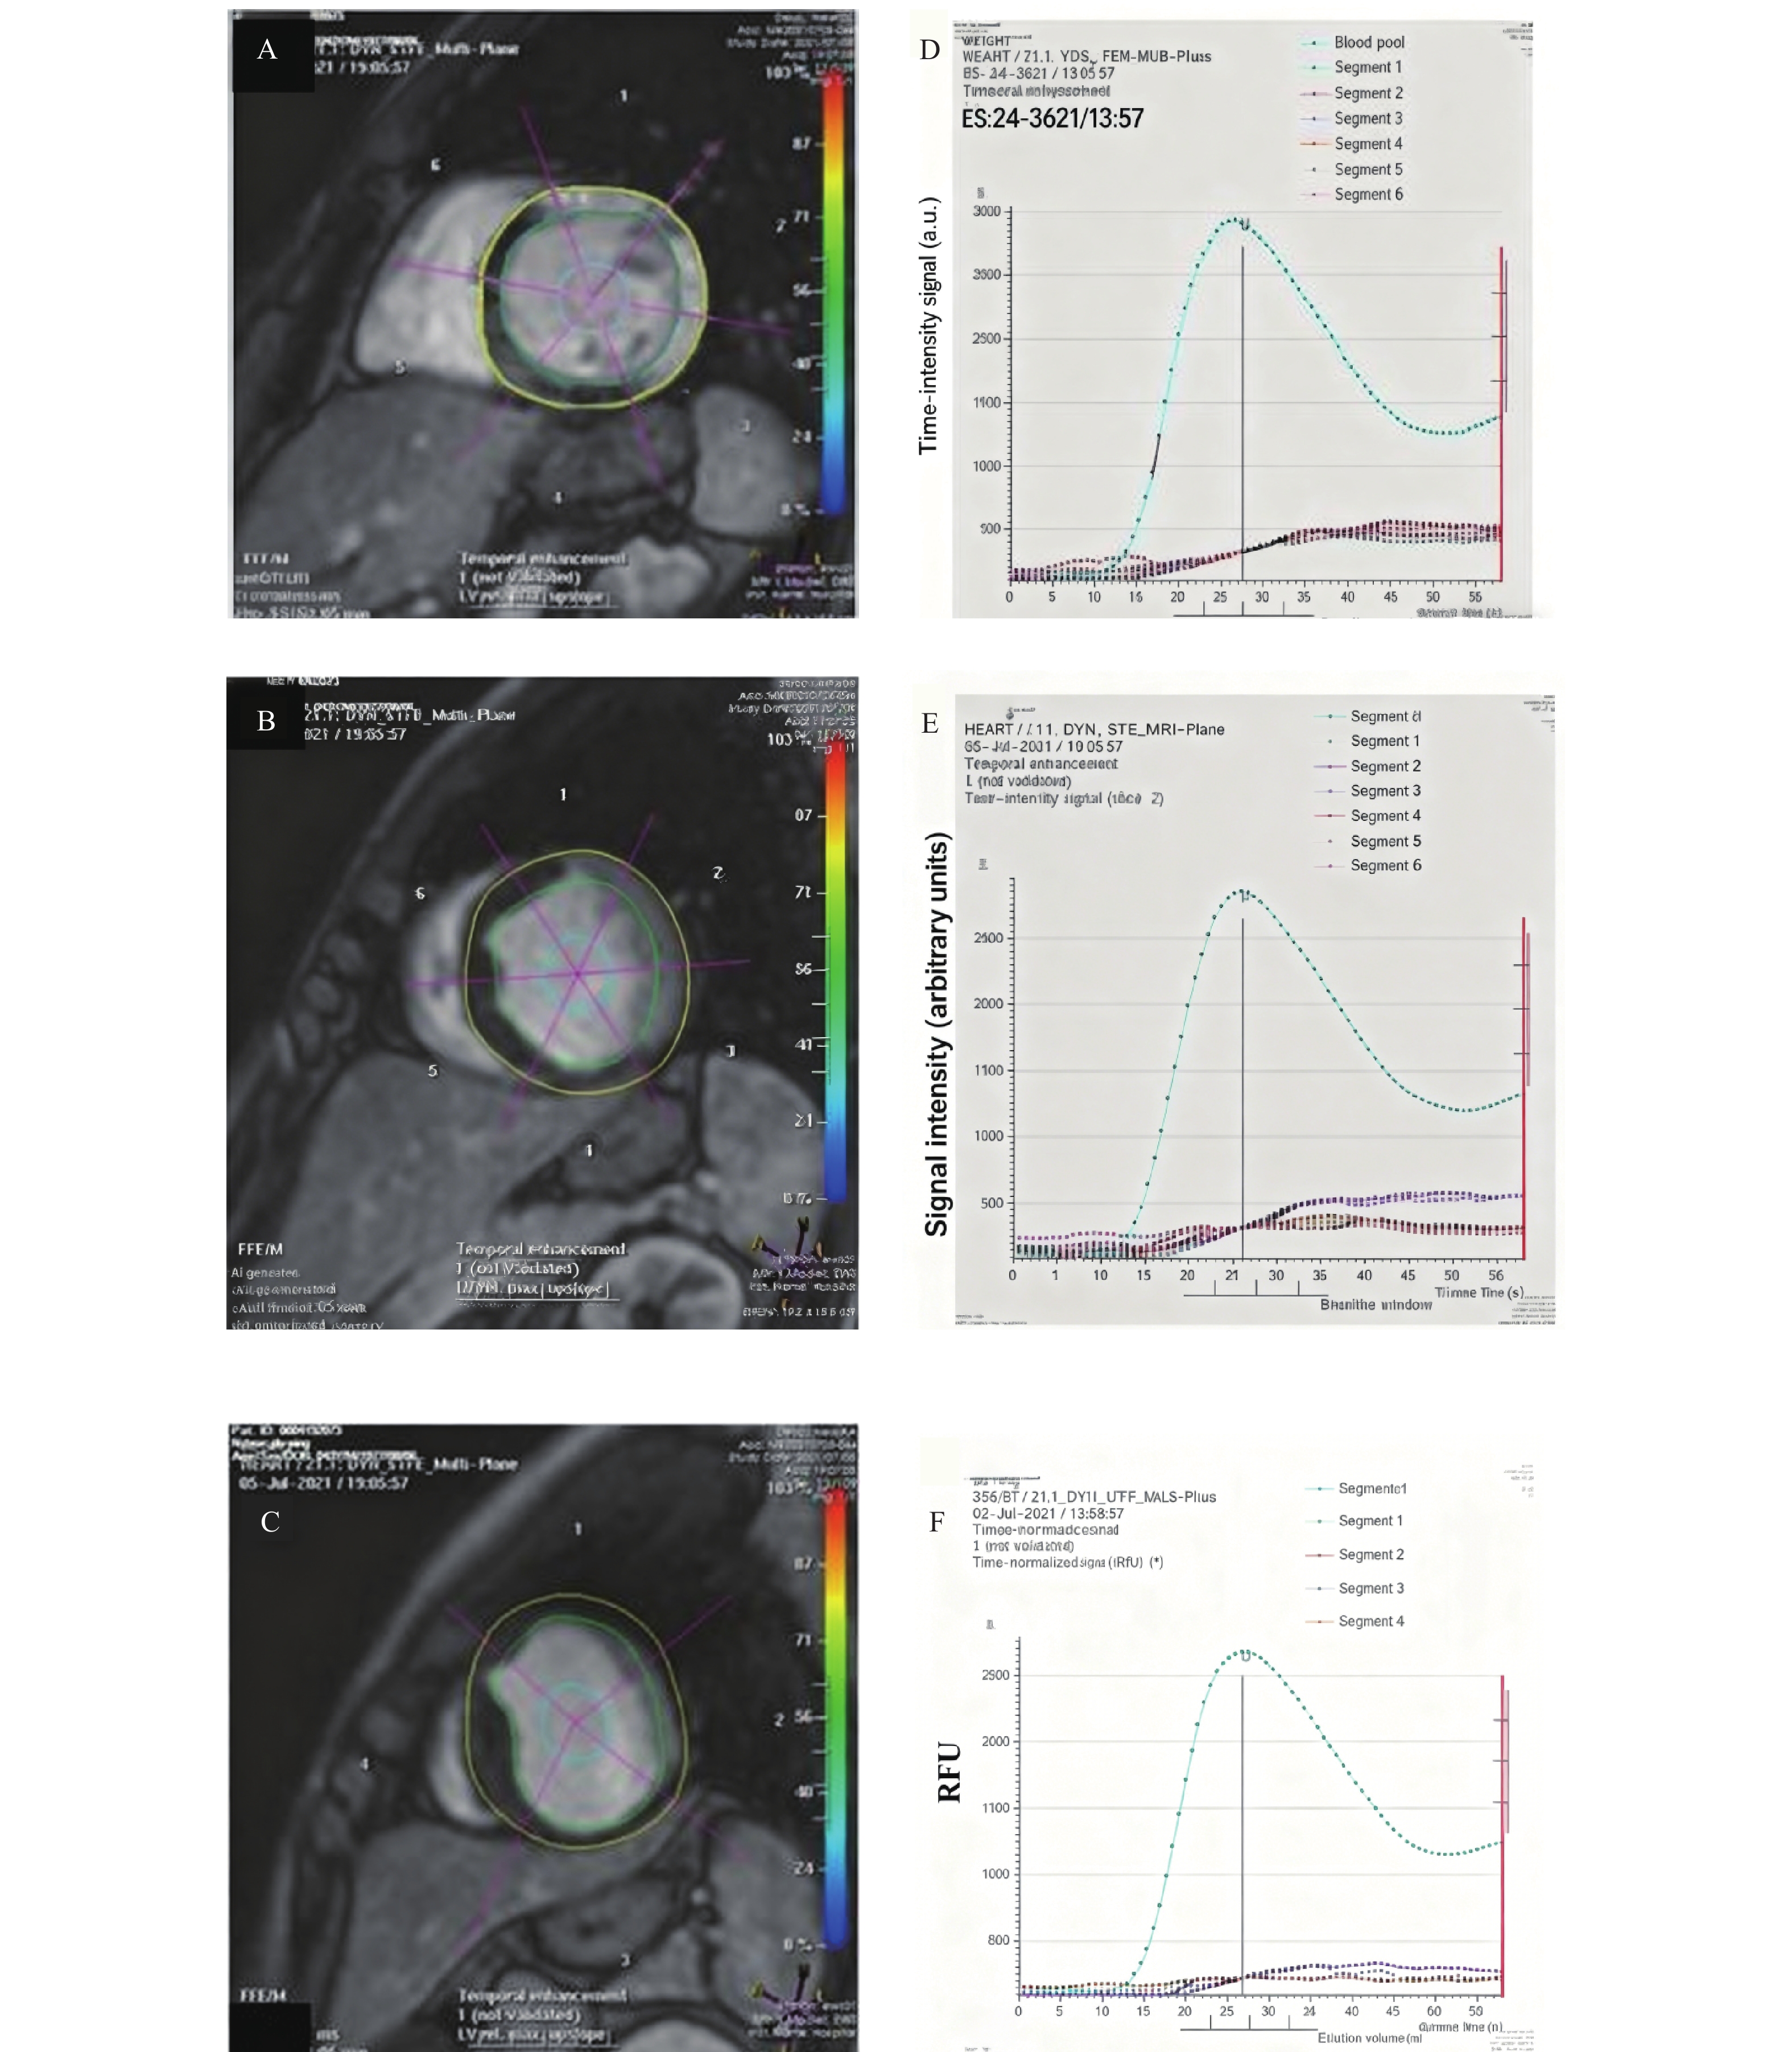

Correlation between T1-mapping and Feature Tracking in Hypertrophic Cardiomyopathy

Yan ZHANG, Lei YANG, Na LI, Mingjie PANG

2026, 47(4): 75-82. doi: 10.12259/j.issn.2095-610X.S20260409

Abstract:

Objective  To explore the correlation between T1-mapping and feature tracking in patients with Hypertrophic Cardiomyopathy (HCM).   Methods  Cardiac magnetic resonance (CMR) data were retrospectively collected from 86 HCM patients hospitalized at Yunnan Provincial First People's Hospital between January 2016 and July 2021. The differences in T1 values before and after contrast enhancement, extracellular volume (ECV), longitudinal strain (LS), circumferential strain (CS), radial strain (RS), and strain rate parameters were compared between the late gadolinium enhancement (LGE)-positive group (59 cases) and LGE-negative group (27 cases).   Results  (1) Patients in the LGE-positive group were younger with a higher proportion of NYHA class III-IV, larger end-diastolic maximal wall thickness, and greater left ventricular mass index (P < 0.05); (2) Pre-contrast T1 values were higher in the LGE(+) group compared to the LGE(-) group, and ECV values were elevated in the LGE-positive group (P < 0.05); (3) In the LGE-positive group, global longitudinal strain (GLS) showed negative correlations with left ventricular mass index, left ventricular end-diastolic maximal wall thickness, LGE%, T1 value, and ECV (r = −0.418, P = 0.008; r = −0.711, P = 0.021; r = −0.621, P = 0.015; r = −0.372, P = 0.020; r = −0.583, P = 0.010, respectively).   Conclusion  In HCM patients with myocardial enhancement, GLS is reduced in LGE-positive cases, which shows significant negative correlations with left ventricular end-diastolic volume, left ventricular mass index, end-diastolic maximal wall thickness, LGE%, and pre-contrast T1 value and ECV.